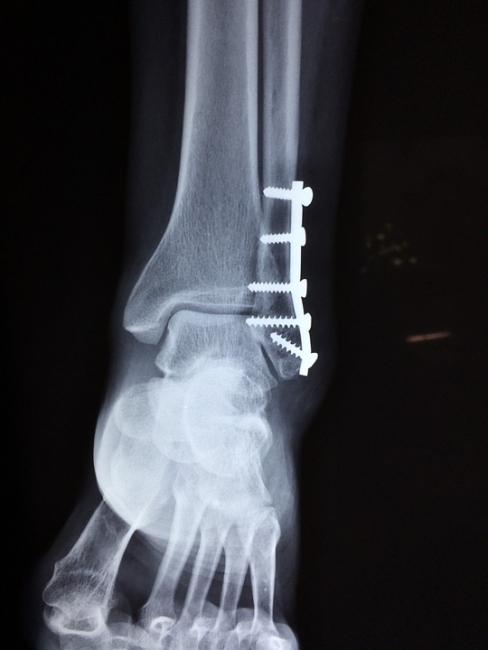

В специализацию травматолога входит профилактика и лечение травм костей, суставов и мягких тканей. Если человек получает перелом, сильный ушиб или вывих, разрыв связок, то обращается именно к этому врачу. Травматолог определит тяжесть полученной травмы и необходимую в конкретном случае методику лечения.

К травматологу нужно обращаться в случае перелома или вывиха, при ушибе мягких тканей и деформации конечностей. Если человека беспокоят частые боли в суставах, мышцах или костях, то также нужно обязательно посетить врача. К травматологу отправляются тогда, когда после ушиба долго не проходит боль, а ткани в месте повреждения изменяют свой цвет. Чем раньше больной человек посетит клинику − тем более результативным и лёгким будет лечение. Часто случается так, что после падения или удара человек не ощущает боли и думает, что помощь врача не требуется. На самом деле лучше сразу посетить его, ведь скрытая травма может представлять огромную опасность.